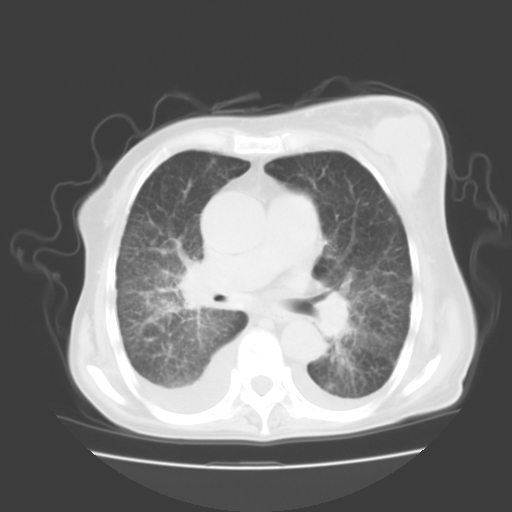

女70y乳腺ca(针吸活检)

肺部病变为淋巴转移,肝脏转移,及局部淋巴转移。胸水可能为淋巴回流受阻(血性的考虑胸膜转移)

癌性淋巴管炎,肝脏转移,瓷胆囊

1)左侧乳腺癌并左侧腋窝及纵隔淋巴结转移,两肺淋巴道转移(癌性淋巴管炎),肝脏多发性转移。2)双侧胸腔积液。3)慢性胆囊炎。

3、双肺癌性淋巴管炎;

5、肝转移瘤;